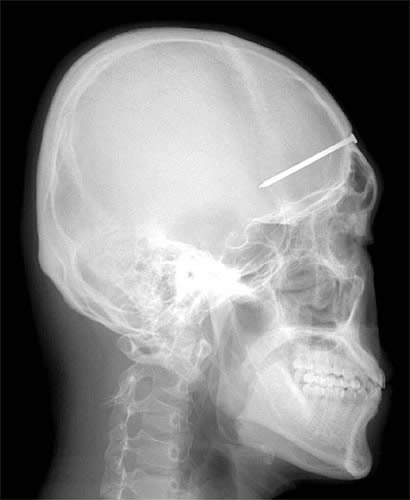

این نوزاد 17 ماه پس از زمین خوردن دسته کلید پلکش رو پاره می کنه و وارد جمجه اش میشه ولی جالب اینه که کره چشمش آسیب دائمی نمیبینه!!!!!

این آقا که یک کارگر ساختمانی هست میره پیش دندانپزشک و میگه فک بالام درد می کنه بعد اقای دکتر میبینه بلهههههههههههههههههههه یک میخ 10 سانتیمتری داخل فک بالای این اقا هست و ایشون نمی دونن چطوری این میخ 6 روز پیش وارد فکش شده!!!!!!!!!!!!!!!